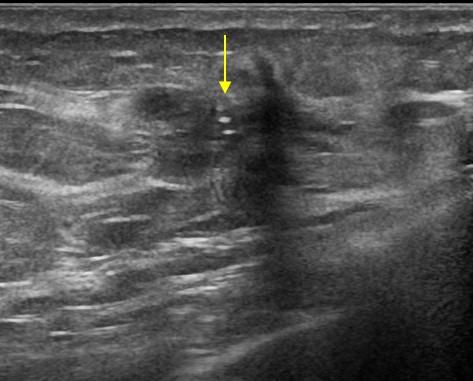

Ung thư vú

Ung thư vú - Ảnh 3

» Thông tin: Nữ giới – 52 tuổi.

» Lâm sàng: Khối tuyến vú.